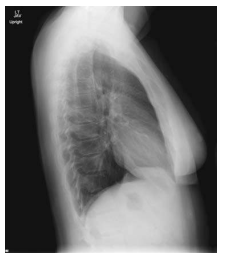

What chest position is this?

Lateral